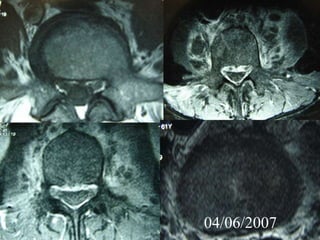

4th case

D.N.

M 61– Cardiologist

Symptoms

 Severe Neurologic deficit

 Intensive Thoracic-lumbar Pain

 High fever

Laboratory

 Neutroph. ↑

 SR 60

PMH

 Heavy smoker

 Diabetes melitus

 Recent Elbow Furuncle (untreated)

Elbow furuncle

3

4 4

04/06/2007

13/06/2007